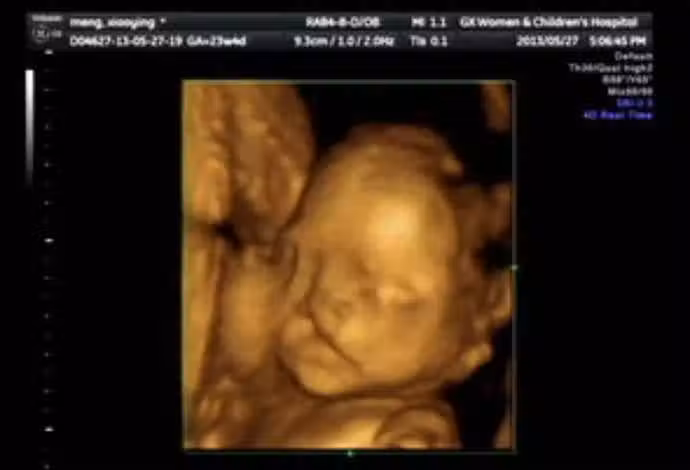

懷孕6個月!23歲孕媽照超音波「寶寶一直在笑」 醫生皺眉勸:「孩子不能留」...

圖片來源:ETtoday

突如其來的消息,讓年輕媽媽瞬間崩潰,不明白自己在孕期明明很注意了,為何還會有問題呢?後來經過詳細了解後,醫生終於找到了問題根本,原來女子在婚前的生活十分豐富,不但經常和朋友喝酒玩樂,甚至還菸不離手。雖然說婚後減少了許多夜生活,但是吸菸這麼多久,早就已經難戒掉了,「我在懷孕後也有繼續抽,身邊也有孕期抽菸的朋友,她們生下來的孩子都很健康」,所以她一直以為沒事,抱著僥倖的心態,結果竟然發生了不可挽回的憾事。